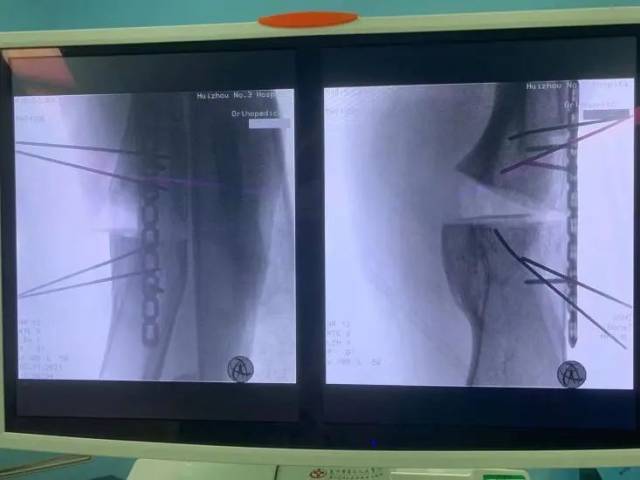

术中截骨后影像

术中,医疗团队按照预定手术思路,首先沿左大腿中下段外侧纵形作皮肤切口,安装股骨前方截骨导板,用摆锯沿截骨导板截断股骨畸形最大处,预留股骨干外侧部分皮质。然后用撑开器沿截骨端将其撑开并放置内侧楔形导板,在C臂机透视下见经截骨矫形后现股骨干向内、向后成角畸形基本恢复,力线基本纠正。最后进行左侧股骨钢板内固定术+左侧髂骨切除术用作移植物+左侧股骨植骨术+左侧股骨人工骨植骨术。整个手术过程非常顺利。